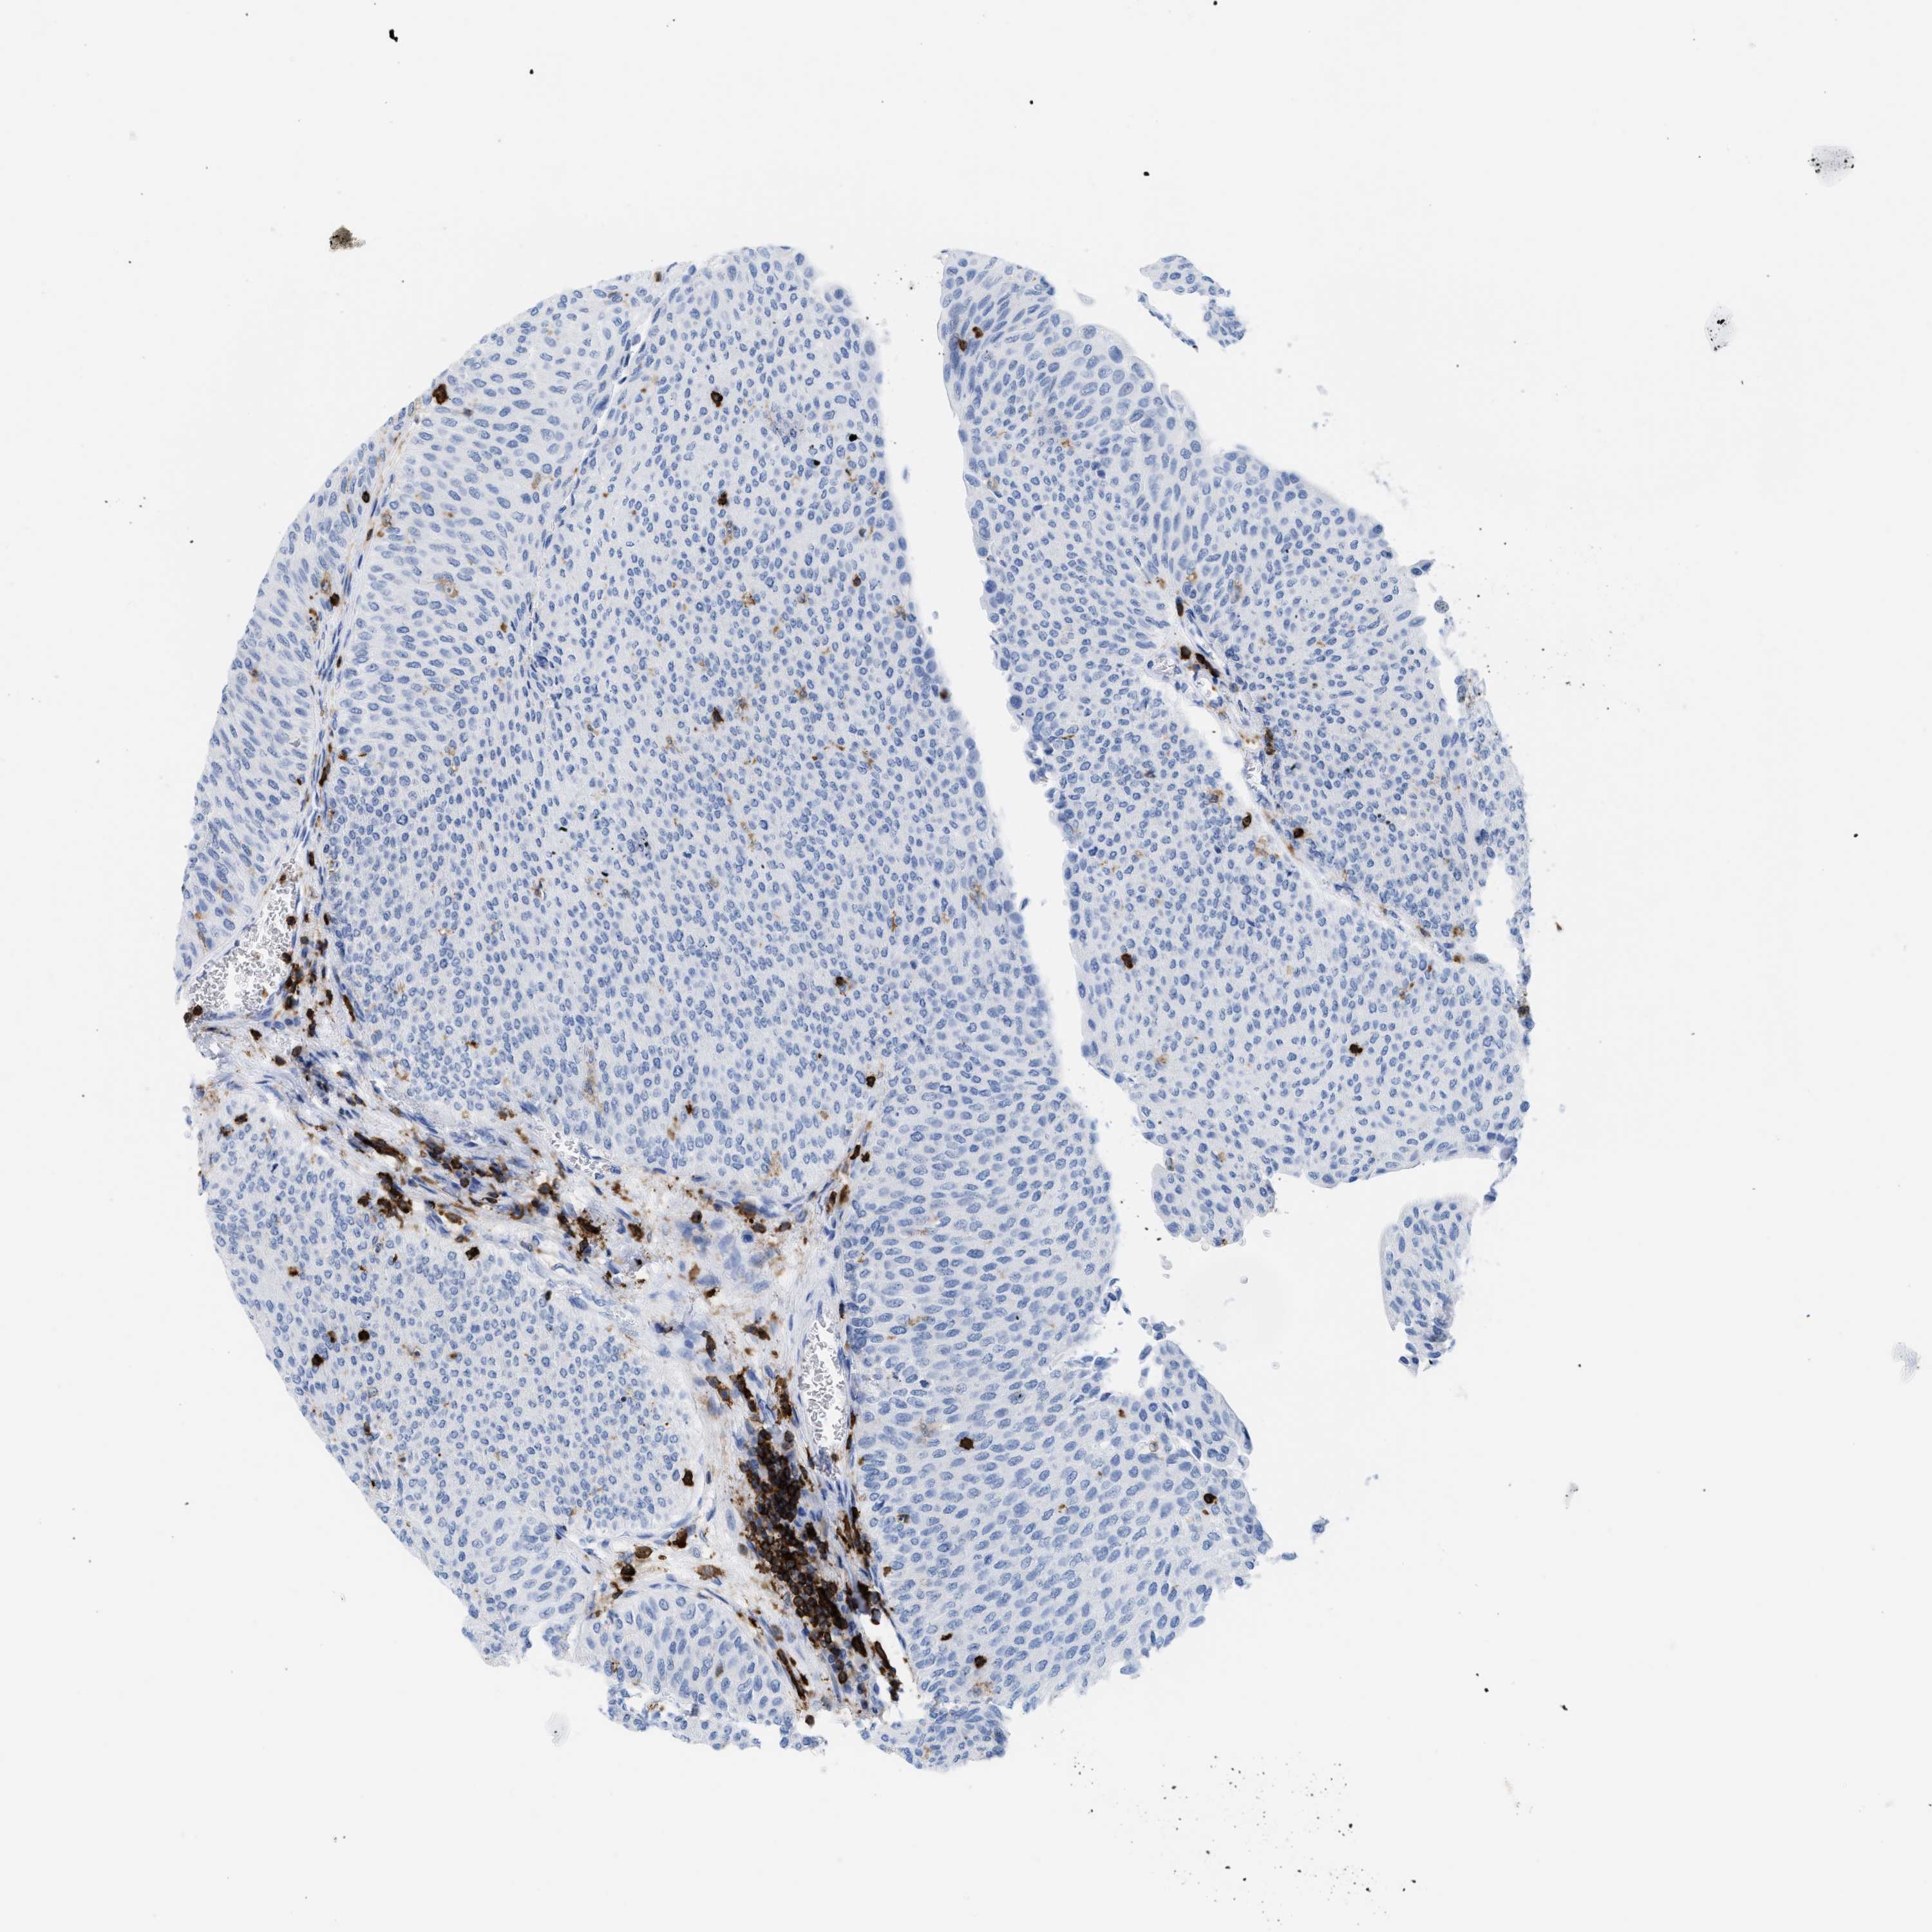

UROTHELIAL CANCER - Protein expressioni

A mouse-over function shows sample information and annotation data. Click on an image to view it in a full screen mode. Samples can be filtered based on level of antibody staining by selecting one or several of the following categories: high, medium, low and not detected. The assay and annotation is described here.

Antibody stainingi

Antibody staining in the annotated cell types in the current human tissue is reported as not detected, low, medium, or high, based on conventional immunohistochemistry profiling in selected tissues. This score is based on the combination of the staining intensity and fraction of stained cells.

Each image is clickable and will lead to virtual microscopy that enables deeper exploration of all samples and also displays staining intensity scores, fraction scores and subcellular localization as well as patient and tissue information for each sample.

Antibody HPA019493

Urothelial carcinoma, Low grade

Urothelial carcinoma, High grade